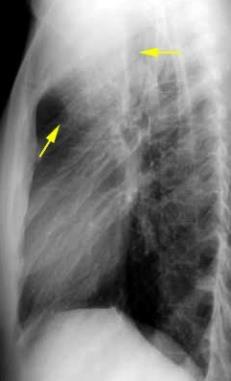

Líneas paraespinales formando un “paréntesis” por encima del diafragma. El signo señala el origen “intratorácico” de la lesión.

Conrad A et al. Pott’s disease associated with large and multiple abscesses in a 30-year-old migrant from Chad. BMJ Case Rep 2018

(lesiones toracoabdominales) La divergencia de las líneas paraespinales apunta a lesión toracoabdominal, que desde el tórax desciende y penetra en el abdomen.

Signo del “iceberg” positivo en Tb vertebral

Afectación por vía hematógena. Región dorsolumbar más frecuente. Afectación inicial: irregularidad de los platillos vertebrales, disminución del disco intervertebral con esclerosis ósea adyacente. Kim. Radiographics.2001